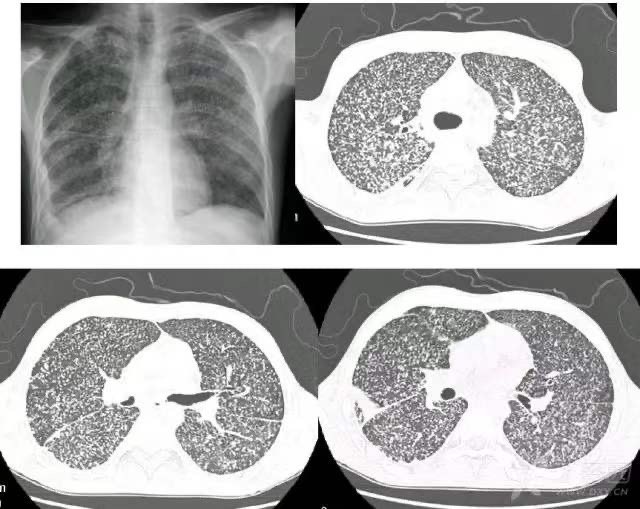

急性血行播散性肺结核:典型的三均。